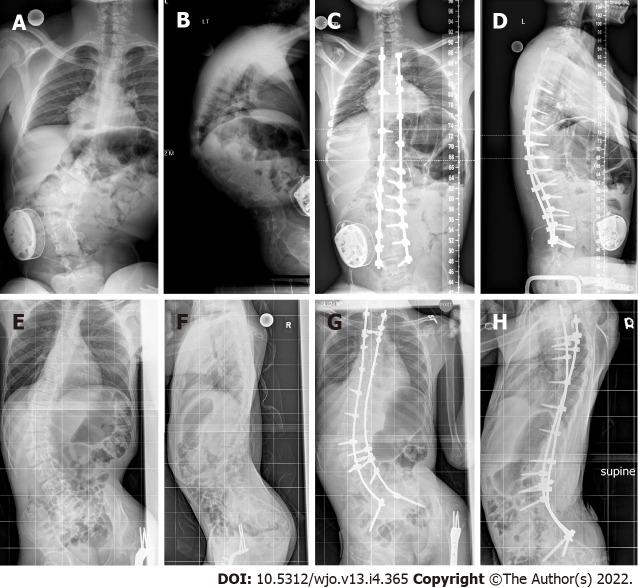

This was a retrospective, cohort study in which we reviewed the medical records of children with cerebral palsy scoliosis treated with posterior instrumentation and fusion at a single institution. Minimum follow-up was six months. Patients were stratified into two groups: Those who were fused to the pelvis and those fused to L4/L5. The major outcomes were complications and radiographic parameters. The former were stratified into major and minor complications, and the latter consisted of preoperative and final Cobb angles, L5-S1 tilt and pelvic obliquity.

The study included 47 patients. The correction of the L5 tilt was 60% in patients fused to the pelvis and 67% in patients fused to L4/L5 ( 0.22). The pelvic obliquity was corrected by 43% and 36% in each group, respectively ( = 0.12). Regarding complications, patients fused to the pelvis had more total complications as compared to the other group (63.0% 30%, respectively, = 0.025). After adjusting for differences in radiographic parameters (lumbar curve, L5 tilt, and pelvic obliquity), these patients had a 79% increased chance of developing complications (Relative risk = 1.79; 95%CI: 1.011-3.41).

Including the pelvis in the distal level of fusion for cerebral palsy scoliosis places patients at an increased risk of postoperative complications. The added value that pelvic fusion offers in terms of correcting pelvic obliquity is not clear, as these patients had similar percent correction of their pelvic obliquity and L5 tilt compared to children whose fusion was stopped at L4/L5. Therefore, in a select patient population, spinal fusion can be stopped at the distal lumbar levels without adversely affecting the surgical outcomes.